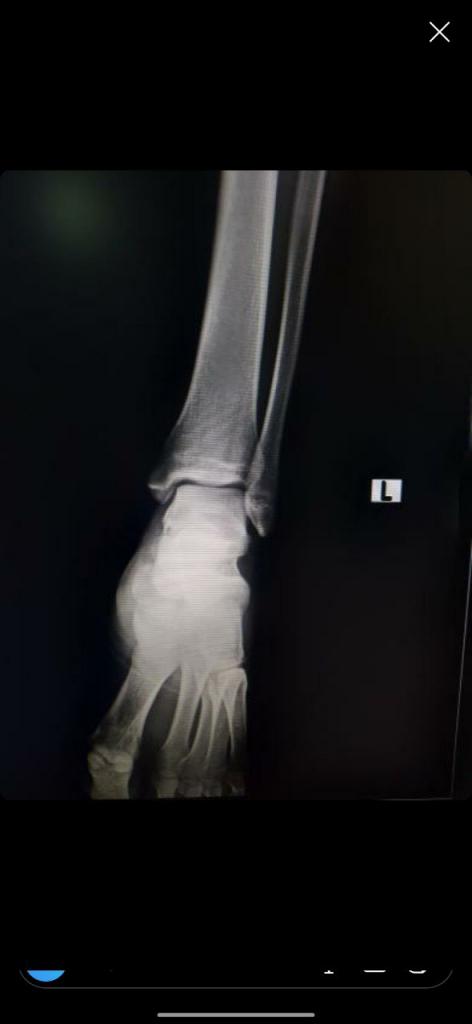

Нажмите на изображение для увеличения

Название: IMG_20200204_214003_668.jpg

Просмотров: 26

Размер:	20.8 Кб

ID:	13293269Нажмите на изображение для увеличения

Название: IMG_20200204_214000_006.jpg

Просмотров: 29

Размер:	21.2 Кб

ID:	13293270Дорогие врачи! Как по вашему, тут есть трещина?

Заранее спасибо!

Цитата Сообщение от Люси Посмотреть сообщение

Вложение 13293269Вложение 13293270Дорогие врачи! Как по вашему, тут есть трещина?

Нужны более качественные снимки. Сами снимки, может, и ничего, а вот их фото, плохого качества и маленькое. Мы ищем мельчайшие детали, а тут все маленькое и как в тумане)) По этим снимкам трещины не вижу, но и исключить не могу. Если есть в электронном виде, то выложите их.